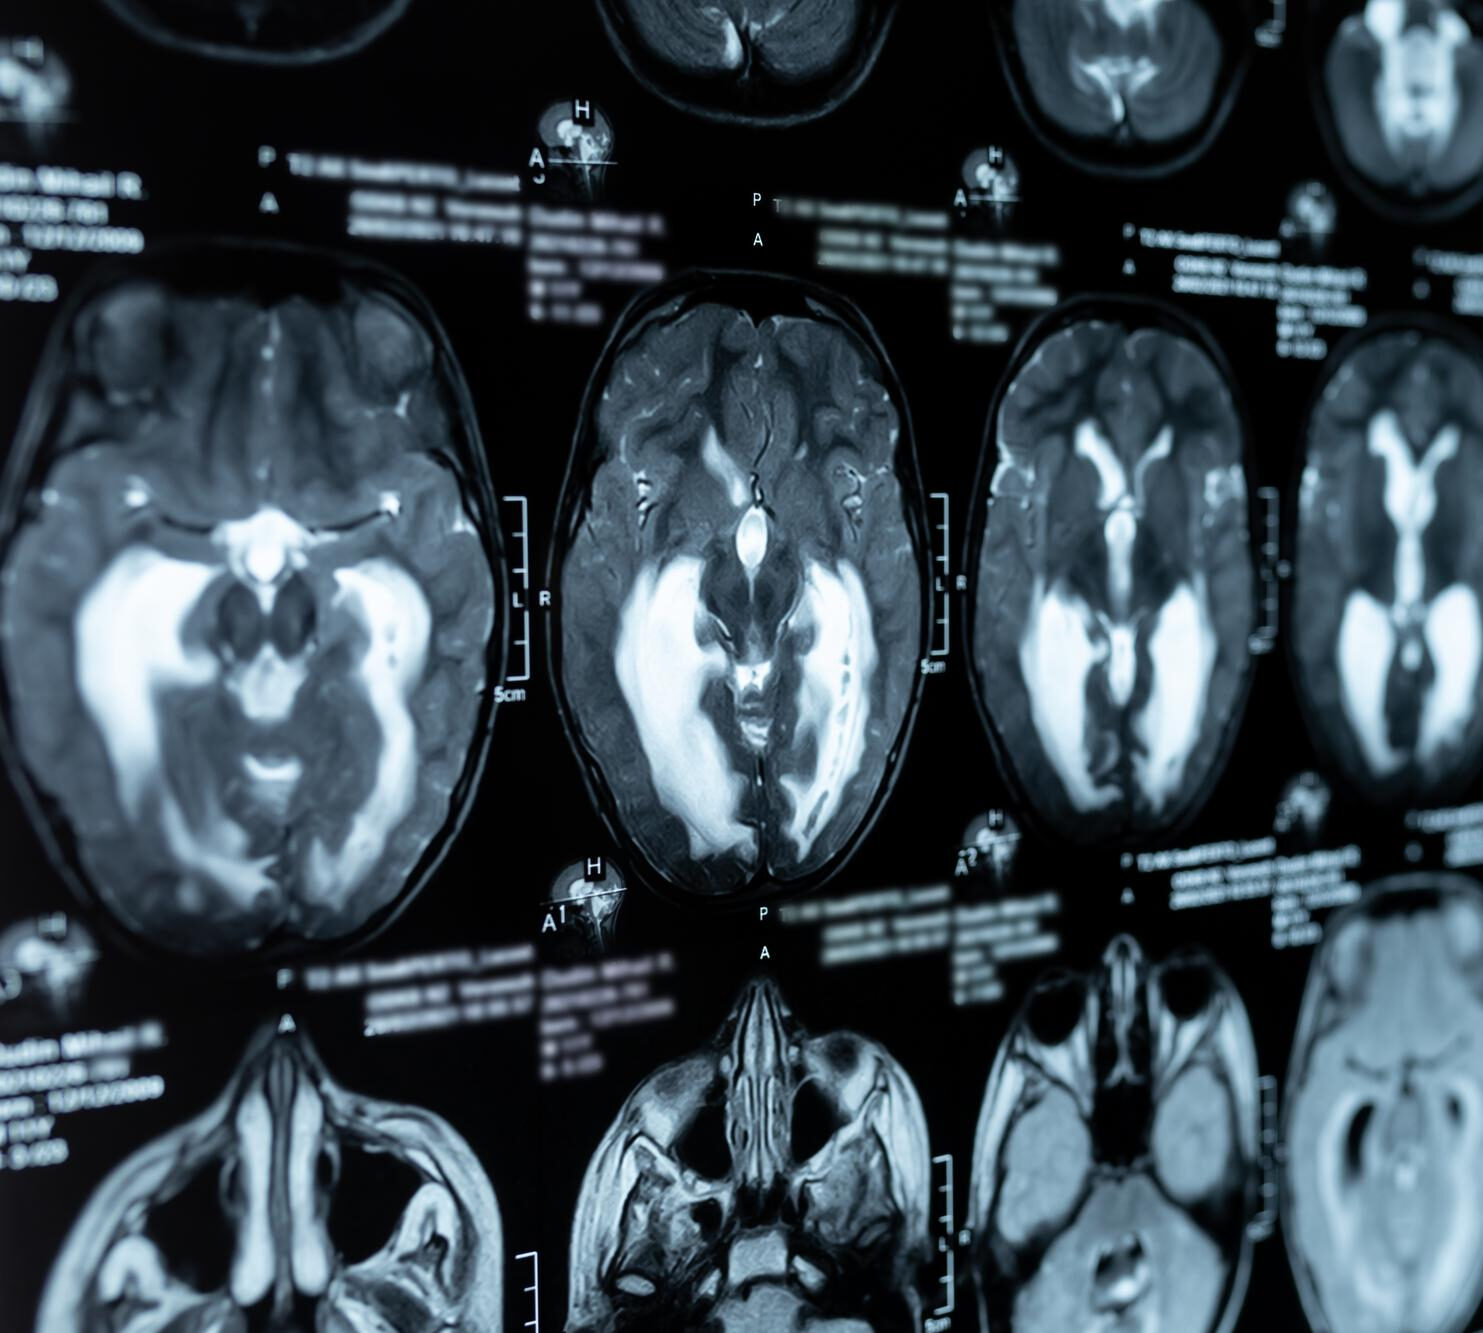

Fear is a natural response that keeps us safe from danger in our environments. However, problems with the natural fear response – for example, in post-traumatic stress disorder – can affect a person’s quality of life. In these studies, we want to investigate how the brain learns to fear by examining the brain in three different ways.

- Avoidance study: This study will investigate how our brain learns about avoidance responses, emotional learning, and memory using functional MRI scans.

Avoidance study: This study will investigate how our brain learns about avoidance responses, emotional learning, and memory. This study includes 3 visits:

- Two fMRI scans (about 2 hours each, on two consecutive days)

- One session of TMS + fMRI (about 2 hours)

- Two fMRI scans (about 2 hours each)